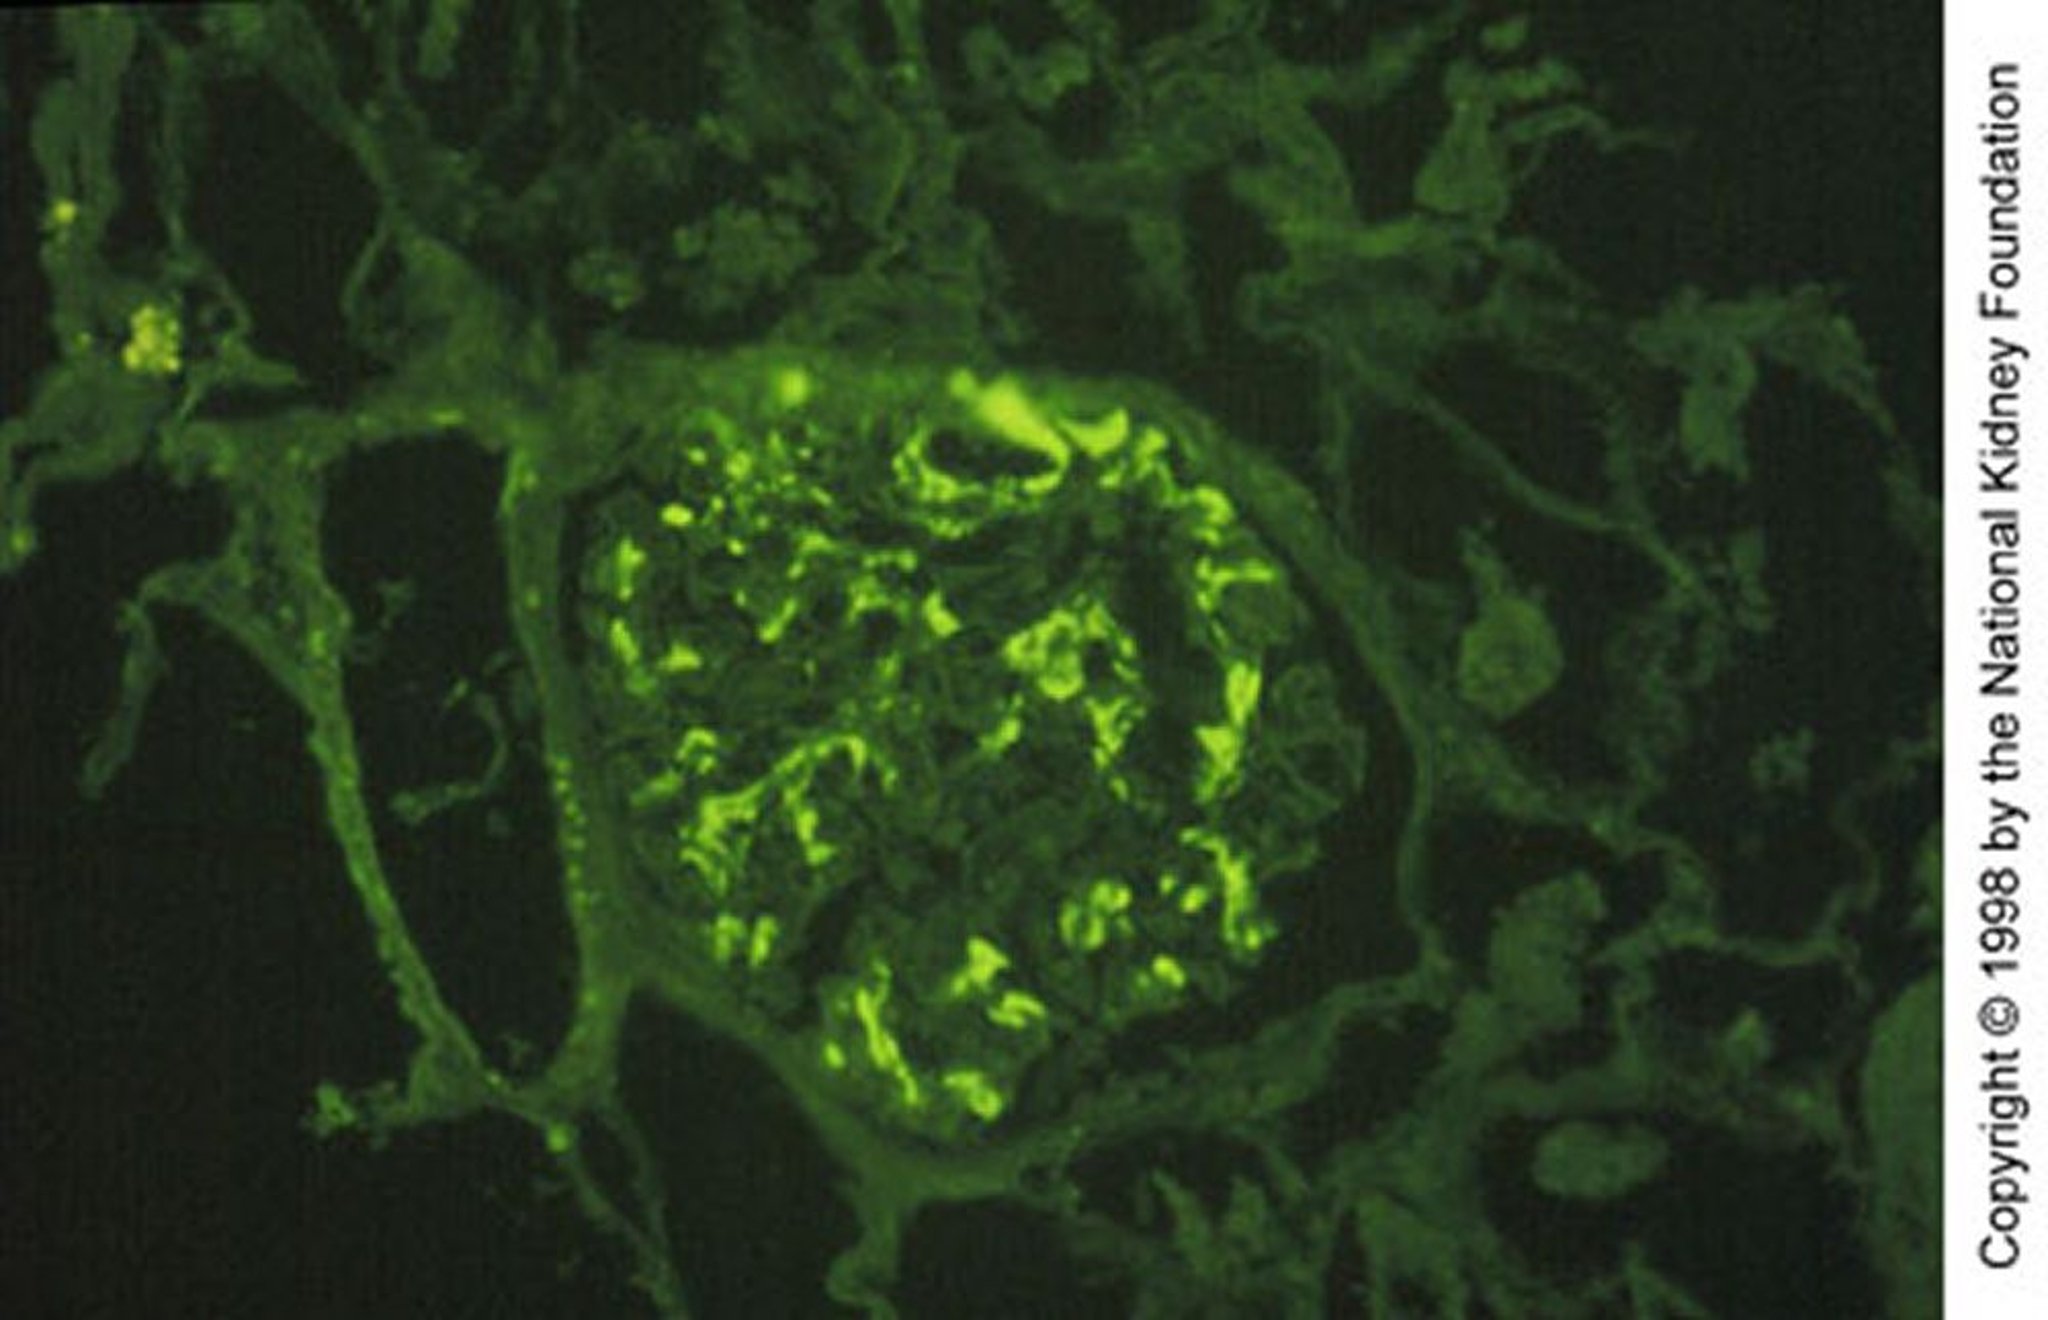

Image provided by Agnes Fogo, MD, and the American Journal of Kidney Diseases' Atlas of Renal Pathology (see www.ajkd.org).

Биопсия почек показывает гранулярные включения IgA и комплемента (СЗ) при иммунофлюоресцентном окрашивании в расширенном мезангии с очагами сегментарных пролиферативных или некротических изменений. Важно отметить, что мезангиальные отложения IgA неспецифичны и встречаются также и при многих других заболеваниях, включая иммуноглобулин А-васкулит, цирроз печени, воспалительные заболевания кишечника, целиакию, псориаз, ВИЧ-инфекцию, рак легких и некоторые системные ревматические заболевания.